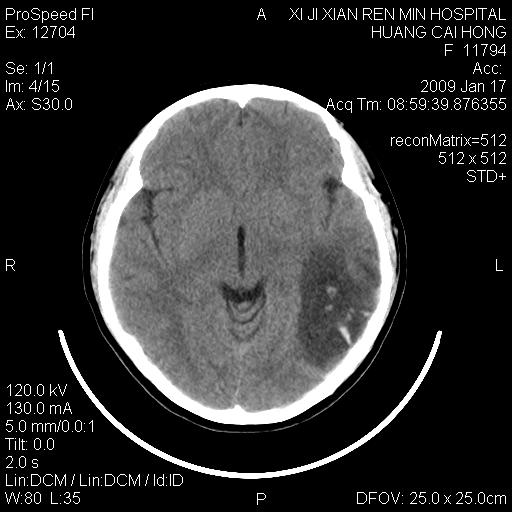

以下是引用zbp537在2009-1-19 13:54:00的发言:[br]首先考虑脑炎。[br]诊断依据:[br]1、患者较年轻。[br]2、有感冒病史。[br]3、左侧颞枕叶这么大一片低密度影,占位征象却不明显,不符合肿瘤特征,其内的高密度影为出血灶。

以下是引用xiaoniu在2009-1-19 13:29:00的发言:[br]左侧颞叶三角形低密度影,占位效应不明显,其内点片样高密都影,青少年患者,首先考虑:少突胶质瘤。因为有感冒病史,不能除外感染的可能。